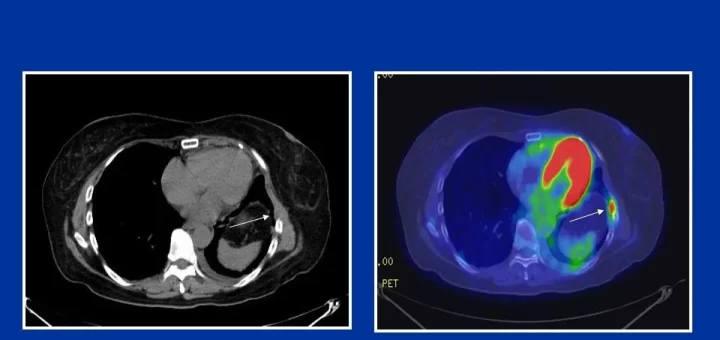

Modern Management of Malignant Liver Tumors: How Interventional Radiology, TACE, and Radiofrequency Ablation Are Transforming Treatment – By Dr. Mahmoud Abdelaziz Ghalab

Malignant liver tumors are among the most serious conditions affecting patients across the Arab world. Early diagnosis and choosing the right treatment strategy can significantly improve outcomes and quality of life. As an interventional...